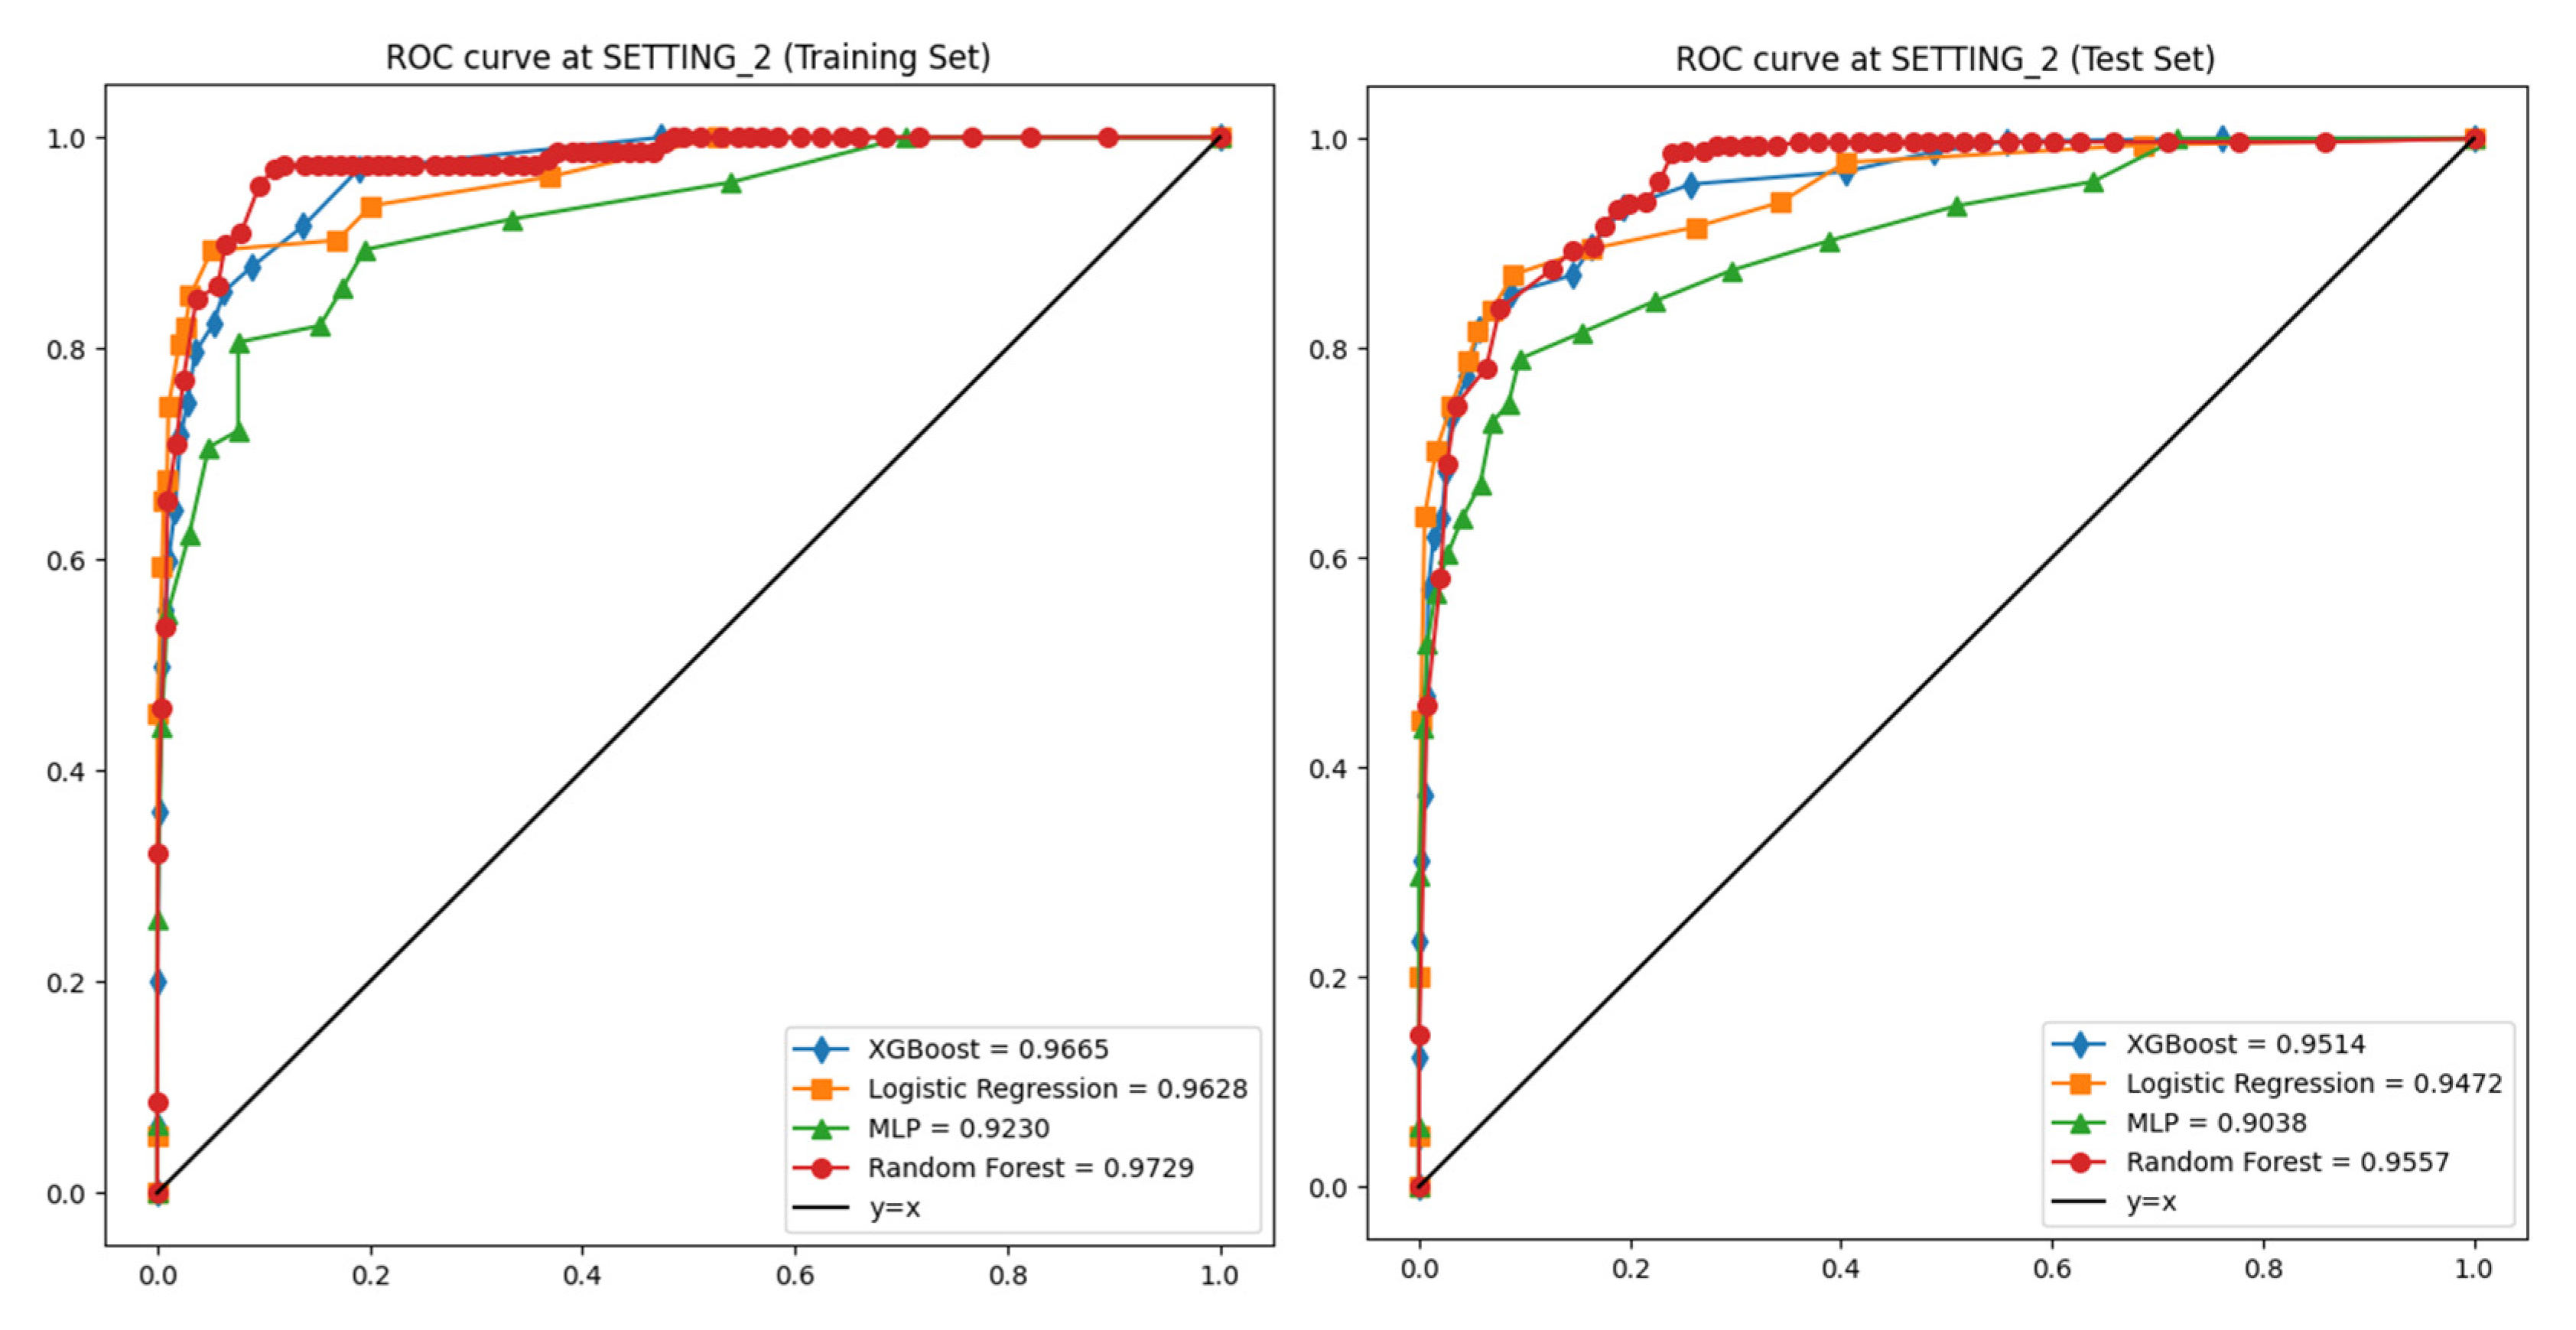

3.2. Performances of Machine Learning Models

| SETTING_2 | Logistic Regression | 0.973 | 0.992 | 0.898 | 0.903 | 0.901 | 0.963 |

| Random Forest | 0.99 | 0.992 | 0.906 | 0.93 | 0.918 | 0.973 | |

| XGBoost | 0.993 | 0.996 | 0.917 | 0.888 | 0.902 | 0.967 | |

| Multi-Layer Perceptron | 0.972 | 0.975 | 0.921 | 0.892 | 0.706 | 0.923 |

| SETTING_2 | Logistic Regression | 0.951 | 0.987 | 0.606 | 0.825 | 0.693 | 0.947 |

| Random Forest | 0.966 | 0.982 | 0.737 | 0.731 | 0.731 | 0.956 | |

| XGBoost | 0.962 | 0.987 | 0.661 | 0.796 | 0.72 | 0.951 | |

| Multi-Layer Perceptron | 0.961 | 0.978 | 0.748 | 0.716 | 0.723 | 0.904 |

| Fold | Training Accuracy | Validation Accuracy | Training AUC | Validation AUC |

|---|---|---|---|---|

| 1 | 0.973 | 0.968 | 0.981 | 0.962 |

| 2 | 0.978 | 0.959 | 0.984 | 0.953 |

| 3 | 0.975 | 0.964 | 0.983 | 0.959 |

| 4 | 0.982 | 0.971 | 0.987 | 0.964 |

| 5 | 0.979 | 0.967 | 0.985 | 0.961 |

| Mean | 0.977 ± 0.003 | 0.966 ± 0.004 | 0.984 ± 0.002 | 0.960 ± 0.004 |